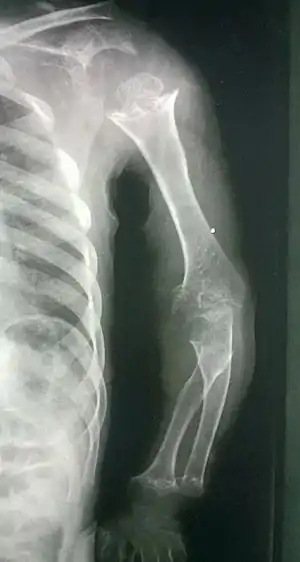

| Pseudoachondroplasia. Shoulders and Humeri. Note the dysplastic proximal humeral epiphyses, metaphyseal broadening, irregularity and metaphyseal line of ossification. These changes are collectively known as "rachitic-like changes". Lesions are bilateral and symmetrical. | |

- Dysplastic/hypoplastic epiphyses especially of shoulders and around the knees.

- Metaphyseal broadening, irregularity and metaphyseal line of ossification. These abnormalities that are typically encountered in proximal humerus and around the knees are collectively known as “rachitic-like changes”.

- Radiographic lesions of the appendicular skeleton are typically bilateral and symmetric.